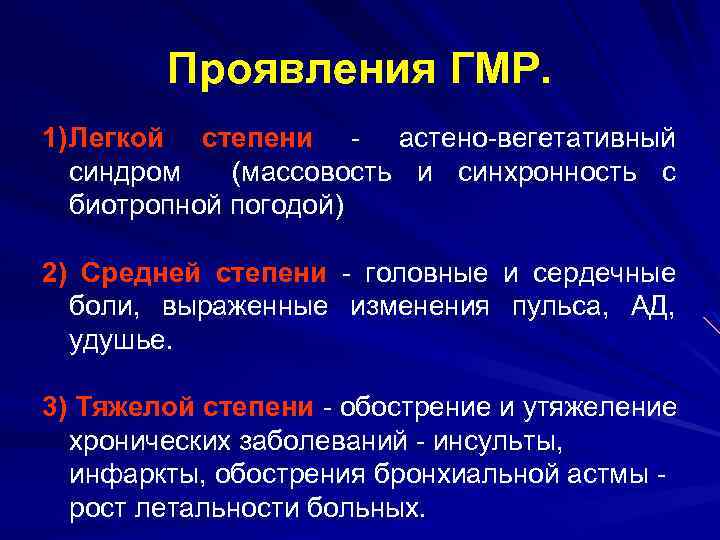

Классификация синдрома длительного раздавливания: основные категории и признаки